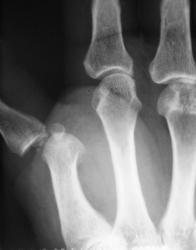

Катенёв Валенти... Дата публикации 01.05.2009, 12:06 Пациент направлен хирургом с диагнозом "перелом". Произвели рентгенографи. Вопрос заключается в том, что данное состояние должно быть обозначено, как "вывих" или "переломовывих"? Пт, 01/05/2009 - 12:46 #1 flagman Не на сайте Был на сайте: 11 лет 5 месяцев назад Зарегистрирован: 05.06.2008 - 20:08 Публикации: 83 а если перелом, вывих. Пт, 01/05/2009 - 12:48 #2 Катенёв Валенти... Не на сайте Был на сайте: 7 лет 4 недели назад Зарегистрирован: 22.03.2008 - 22:15 Публикации: 54876 Спасибо за высказанное мнение. Пт, 01/05/2009 - 13:58 #3 Ермолаев Не на сайте Был на сайте: 8 лет 10 месяцев назад Зарегистрирован: 07.02.2009 - 16:33 Публикации: 670 Валентин Львович! Мое мнение, что имеется вывих и перелом. Два разных костно-травматических изменения с точки зрения патологической анатомии. dok Пт, 01/05/2009 - 14:00 #4 Катенёв Валенти... Не на сайте Был на сайте: 7 лет 4 недели назад Зарегистрирован: 22.03.2008 - 22:15 Публикации: 54876 Спасибо за высказанное мнение. Пт, 01/05/2009 - 14:47 #5 Петрович Не на сайте Был на сайте: 7 лет 2 месяцев назад Зарегистрирован: 22.03.2009 - 01:13 Публикации: 3908 Господа и товарищи! Перелом чего? Неоднозначно всё Сб, 02/05/2009 - 14:39 #6 mihail72 Не на сайте Был на сайте: 11 лет 1 месяц назад Зарегистрирован: 20.06.2008 - 17:49 Публикации: 4 Вывих и мелкооскольчатый перелом основания проксимальной фаланги Сб, 02/05/2009 - 15:53 #7 Петрович Не на сайте Был на сайте: 7 лет 2 месяцев назад Зарегистрирован: 22.03.2009 - 01:13 Публикации: 3908 Показал бы кто пальчиком а) мелкие осколки б) откуда откололись. Кортикальный слой кости и его фрагменты должны быть видны чётко! Неоднозначно всё

Валентин Львович! Мое мнение, что имеется вывих и перелом. Два разных костно-травматических изменения с точки зрения патологической анатомии.

Вывих и мелкооскольчатый перелом основания проксимальной фаланги